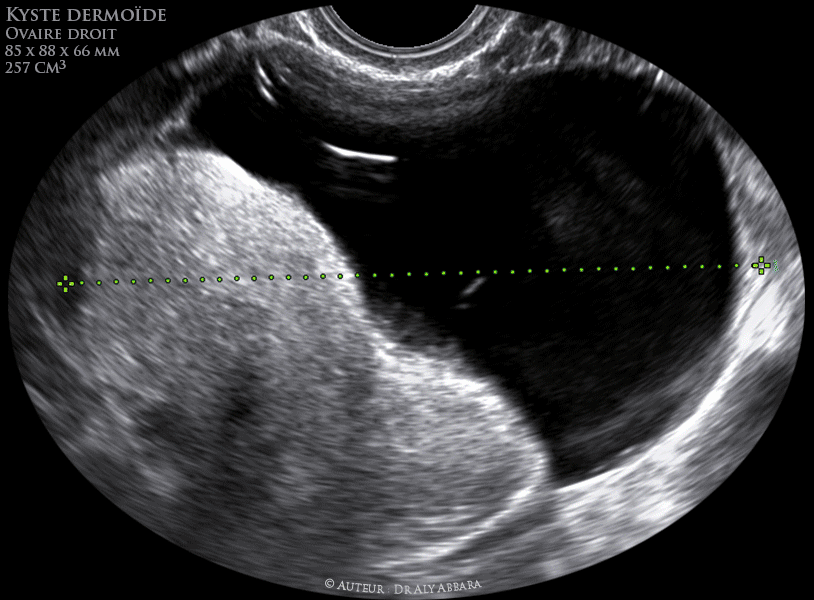

Kyste Dermoide De L Ovaire Mare T L E A A J Uti Lr Gt Rcn Iiiattp Fig 70a Kyste Dermoide De L Ovaire Mare Ovarv Fibrose Le Kyste D Etre Rempli De Poils Emmeles Loug Carti

Ovaire Droit Teratome Benin Kyste Dermoide Compose D Un Pole Liquidien Et Un Autre Hyper Echogene Compose De Poils Et Matiere Grasse Echographie Et Images Cliniques

Ovaire Droit Volumineux Teratome Benin Kyste Dermoide Chez Une Femme Enceinte De 12 Sa Echographie Et Images Cliniques